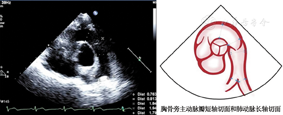

(3)胸骨旁主动脉短轴切面(图4图5图6)

图4

胸骨旁主动脉瓣短轴切面和肺动脉长轴切面,显示舒张末期右心室流出道前后径、肺动脉瓣环内径、肺动脉主干内径和左右肺动脉主干内径测量方法,在肺动脉瓣瓣下2 cm处测量右心室流出道内径,在肺动脉瓣瓣上1 cm处测量肺动脉主干内径,在左右肺动脉主干起始处远心端1 cm处测量左右肺动脉主干内径